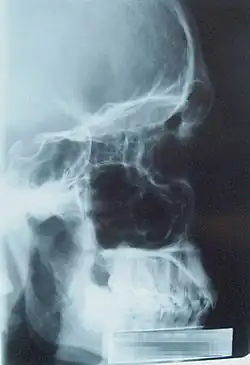

Рентгеновский снимок головы